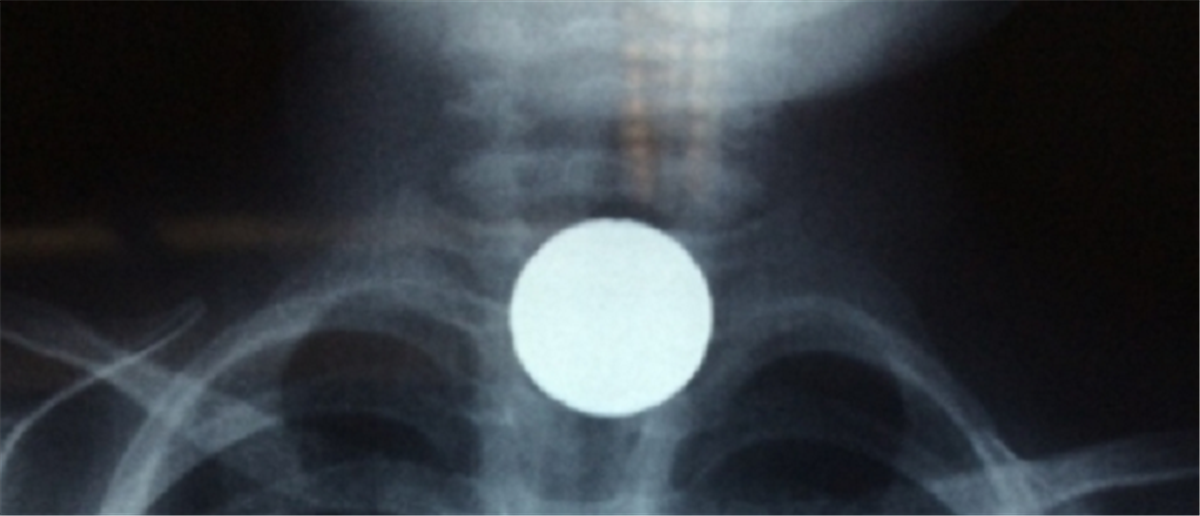

Το κέρμα σφήνωσε στον οισοφάγο του μικρού παιδιού, το οποίο χρειάστηκε να μπει άμεσα στο χειρουργείο...

Εκείνοι τον μετέφεραν αμέσως στο Βενιζέλειο Νοσοκομείο, όπου οι γιατροί έμειναν έκπληκτοι με αυτό που αντίκρυσαν στην ακτινογραφία (φωτό: ekriti).

Το κέρμα είχε σφηνώσει στον οισοφάγο του παιδιού, το οποίο έπρεπε να μεταφερθεί άμεσα στο χειρουργείο για την αφαίρεση του αντικειμένου.